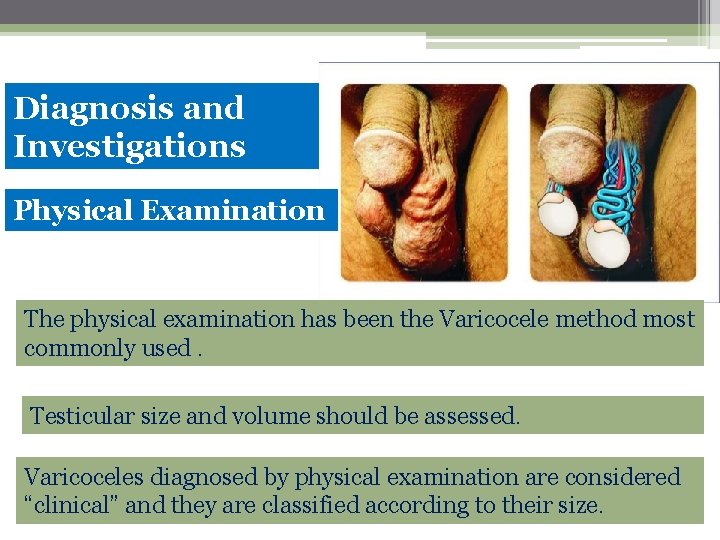

Diagnosis and Investigations Physical Examination The physical examination has been the Varicocele method most commonly used. Testicular size and volume should be assessed. Varicoceles diagnosed by physical examination are considered “clinical” and they are classified according to their size.